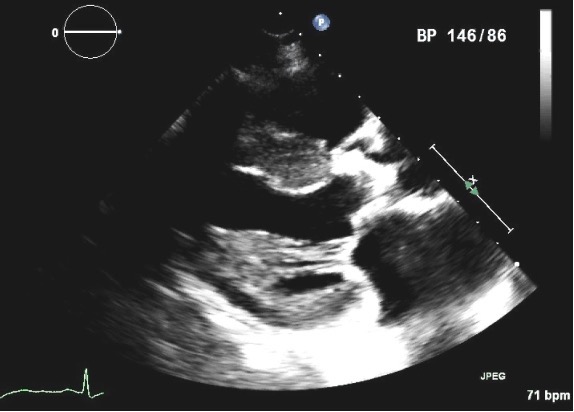

Fig. 9.A mitral pressure half time of